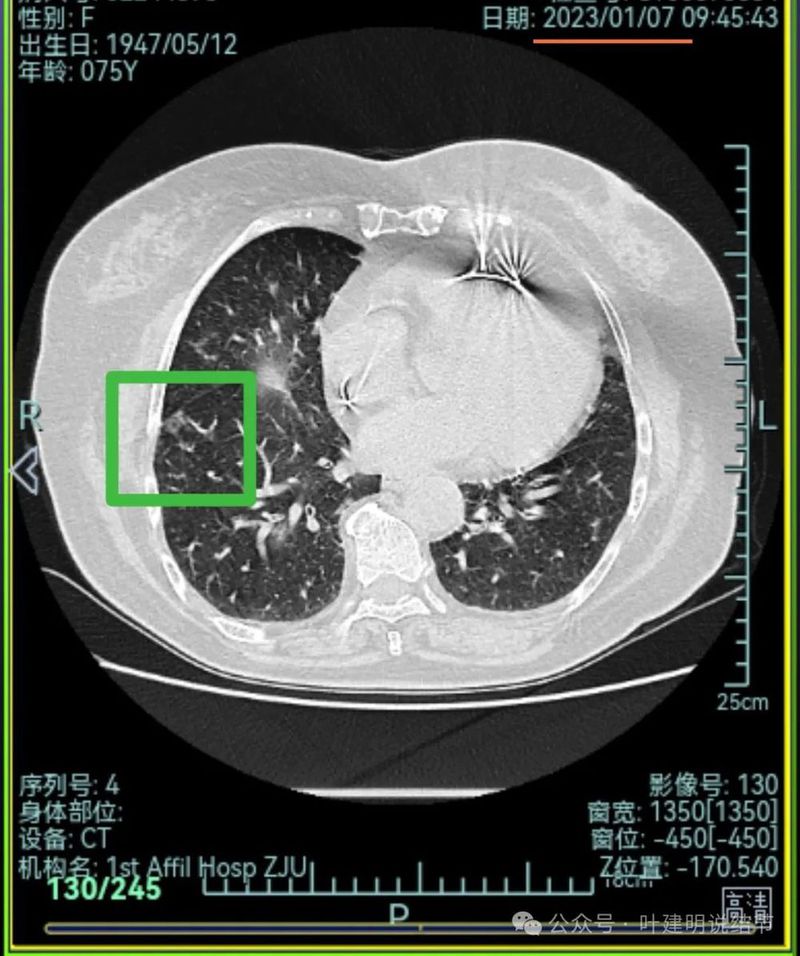

右下混合密度结节,有明显血管进入,轮廓较清,瘤肺边界较清,单灶单处看也像恶性些;

左下胸膜下混合密度结节,边缘不平有毛刺,但毛刺不是很锐利,与胸膜侧紧贴,没有明显牵拉。

右中叶混合密度结节,有血管进入,表面不平,略有胸膜牵拉,但感觉病灶显散,聚拢性不够。

右下叶磨玻璃结节,贴着叶间裂,缺乏收缩力,中间有小空泡,单灶单看恶性不能除外,但略倾向炎性点。

右中叶磨玻璃病灶,轮廓稍糊,瘤肺边界欠清,呈片状,与炎性更符合点。

当时影像考虑:

从上述两肺多发病灶来看,虽有多处也恶性的混合密度结节也是符合的,但由于病灶太多,有的轮廓与边界模糊,首次发现肯定要先考虑感染性病变,并依病毒感染予以治疗并适时复查。因为退一步讲,即使多原发肺癌是这个样子,近80岁的高龄,也肯定不能先考虑手术来解决,那是切不光的。